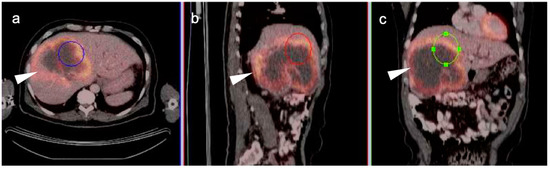

4. Hepatocellular Carcinoma

7. Adrenal Cancer